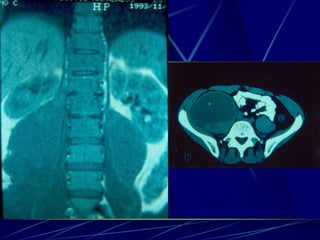

Echinococcus